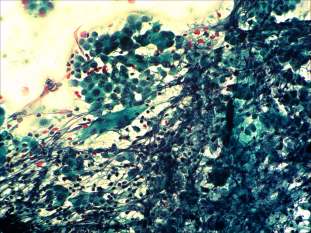

Cytological picture: There was no colloid in the background. Thyrocytes occurred in clusters and dissociated and exhibited oxyphilic metaplasia, prominent nucleoli, intranuclear inclusions and grooves. There were large number of heterogeneous lymphoid and several multinucleated giant cells on the smear.

Cytological diagnosis: papillary carcinoma. Hashimoto's thyroiditis.

Histopathology disclosed a T4 papillary carcinoma and Hashimoto's thyroiditis. The tumor invaded the wall of the trachea but did not brake into.

We gained multiple smears from the tumor. There were signs of Hashimoto's thyroiditis in the presented smear, too, while this was the only finding on other smears.